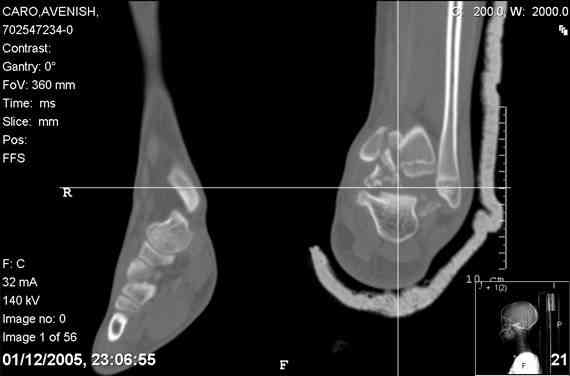

ya by popytalsya sobrat talus anatomichno,seichas pozdno operirovat iz za oteka,po etomy distrakziya apparatom budet optmalna.Posyalu vam podobyai moi sluchai.

14 years old girl

Fall from height ( 3rd floor)